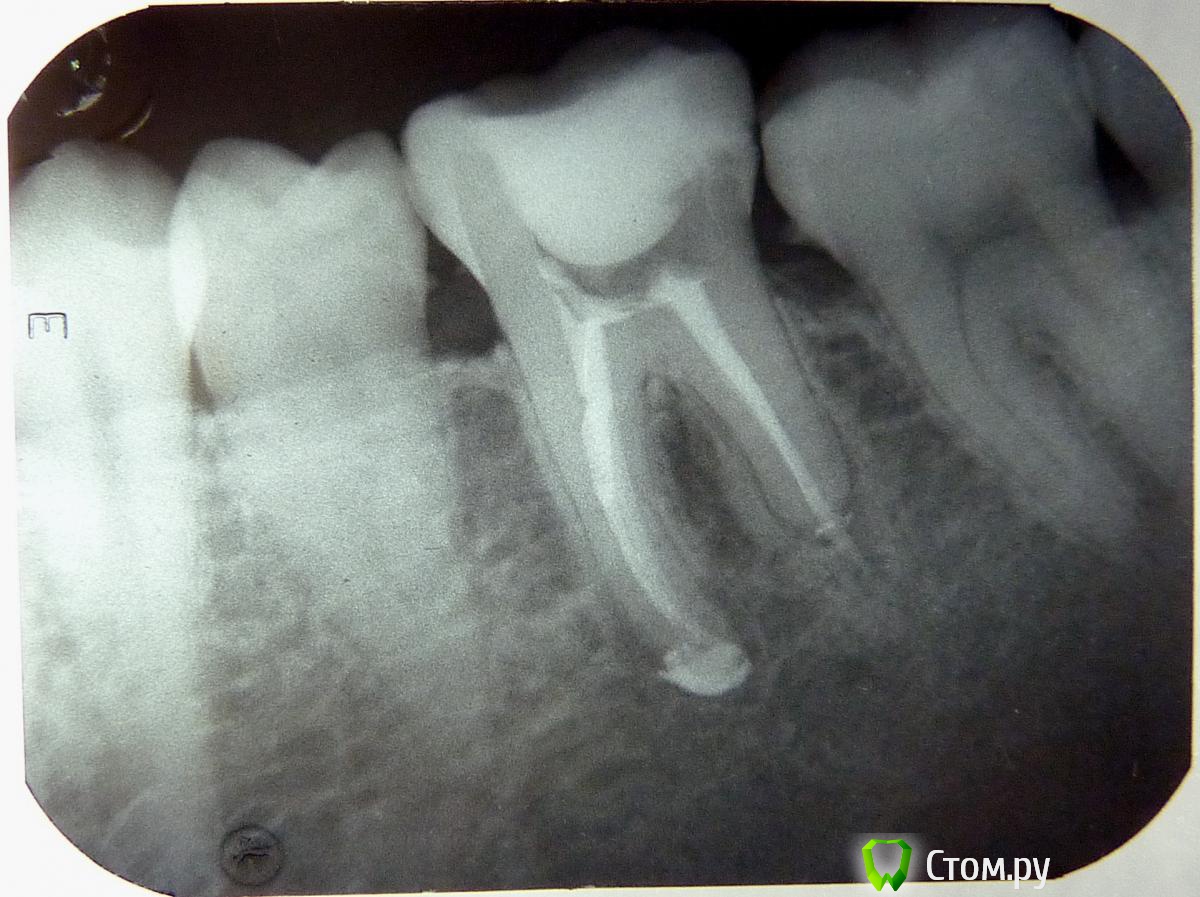

alex_m Опубликовано 7 сентября, 2014 Автор Поделиться Опубликовано 7 сентября, 2014 Вот, сделал фото. Ссылка на комментарий